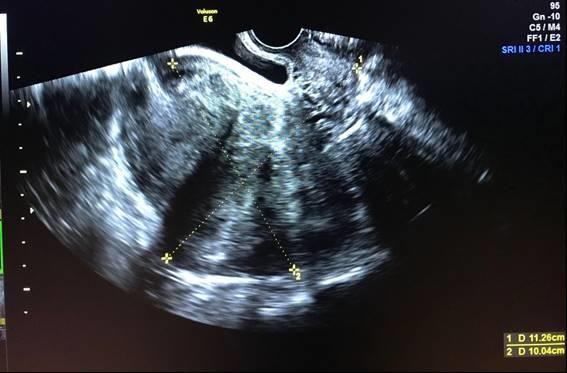

42-year-old patient, G0, came to the medical consultation presenting a 6-month course of pressure at the hypogastric level and menstrual disorders (hypermenorrhea) for 3 months. As a relevant antecedent, the patient referred myomectomy 12 years ago through laparotomy. On physical examination, it was confirmed the presence of a firm mass at the hypogastric level, approximately 5 cm above the pubic symphysis, not painful on palpation and introduced into the pelvic cavity. A transvaginal ultrasound was performed, showing a heterogeneous uterus of 112.6 x 100.4 x 63.2 mm, where at least 4 fibroids were counted (Figure 1):

A) Anterior myoma measuring 24 x 30 mm, type V FIGO classification

B) Posterior myoma measuring 29 x 24 mm, type V FIGO classification

C) Fundic myoma measuring 35 x 25 mm, type VI FIGO classification

D) Left transmural myoma measuring 51 x 40 mm, type III-V, FIGO classification.

Figure 1. Anterior (A) and posterior (B) fibroid (before pregnancy)